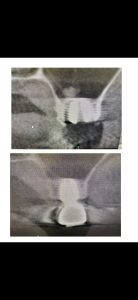

以下の画像は、本日定期検査の方

オペから9ヶ月位の画像、良いね👍👍

デンサーバーでのリフト、採血濃縮血漿板使用

異物の人工骨は一切使わない

目利きある先生方には分かるはず!